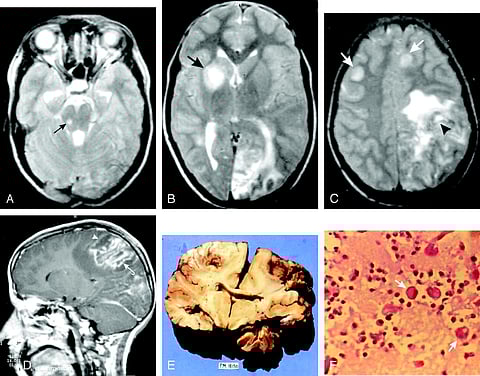

അമീബിക് മസ്തിഷ്ക ജ്വരം

കോഴിക്കോട്: മലപ്പുറം സ്വദേശിയായ പത്തുവയസുകാരന് അമീബിക് മസ്തിഷ്ക ജ്വരം സ്ഥിരീകരിച്ചതായി കോഴിക്കോട് മെഡിക്കൽ കോളെജ് ആശുപത്രി അധികൃതർ അറിയിച്ചു. ബുധനാഴ്ച നടത്തിയ സ്രവ പരിശോധനയിലാണ് രോഗം കണ്ടെത്തിയത്. ഇതോടെ കോഴിക്കോട് മെഡിക്കൽ കോളെജിൽ അമീബിക് മസ്തിഷ്ക ജ്വരം ബാധിച്ച് ചികിത്സയിൽ കഴിയുന്നവരുടെ എണ്ണം 11 ആയി.